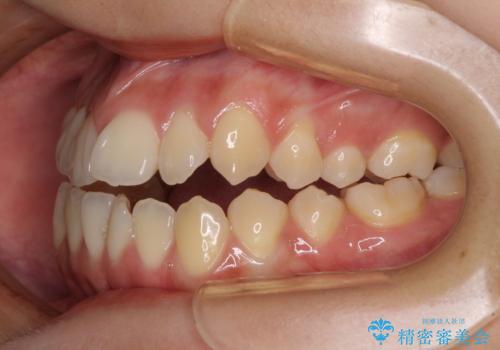

受け口と開咬を急速拡大装置とワイヤー装置で改善

- 前歯の開咬と、受け口による咬み合わせの悪さを気にして来院された患者様です。

上顎歯列が狭窄していたため、急速拡大装置により上顎骨を側方に拡大し、その後ワイヤー装置にて矯正治療を行うこととしました。

舌の突出癖が開咬の原因であったので、改善のための舌トレーニングを行っていただきました。

舌トレーニングは後戻りにも大きく影響するため、とても重要なトレーニングです。